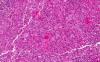

Hematoxylin & eosin

Area 1: The tumor is solidly packed with round to oval cells of comparable size but there is a definitive variation of cellular size. The nuclei are large and have prominent nucleoli. The larger cells have amphophilic cytoplasm and eccentrically located nuclei. In some of the tumor cells, there is a centrally located round inclusion-like, poorly demarcated fibrillary substance that is more dense looking than the surrounding cytoplasm. These inclusion-like bodies are typically contains a substantial amount of vimentin and would be strongly positive for vimentin.

• The tumor is composed of solid sheets of moderate to large cells with large nuclei and prominent nucleoli (Area 1). There is no specific pattern formation. The tumor cells tend to separate from each other. There is some small focal necrosis in this section but the necrosis is more extensive in the part submitted for frozen section (see bonus images below).

• Note that there is significant variation in the size of the cells. Some of them are rather large and has eccentrically located nuclei and big "belly" of cytoplasm.

• Immunohistochemistry demosntrated strong reactivity for vimentin in practically every single cells. Many of the tumor cells are positive for S100 proteins and neurofilament proteins. A much lesser number of tumor cells are positive for glial fibrillary acidic protein (GFAP). The tumor cells are negative for desmin and epithelial membrane antigen (GFAP). Most of the tumor cells are negative for BAF-47. This immunohistochemical profile supports the diagnosis of atypical teratoid rhabdoid tumor (ATRT).